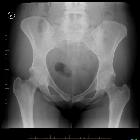

femoroazetabuläres Impingement (Pincertyp)

Pincer morphology refers to an abnormality of the acetabulum or rather an acetabular overcoverage of the femoral head, which may be focal or global, and is one of the causes of femoroacetabular impingement.

AP view of the pelvis and a lateral femoral neck view is recommended for the initial evaluation . Cross-sectional imaging is recommended for the detection of chondral and labral lesions and preoperative planning .

Plain radiograph

Radiographic measures of pincer morphology include the following :

- ilioischial line for assessment of coxa profunda

- increased lateral center-edge angle > 40°

- acetabular index

- crossover sign

- ischial spine sign

- posterior wall sign